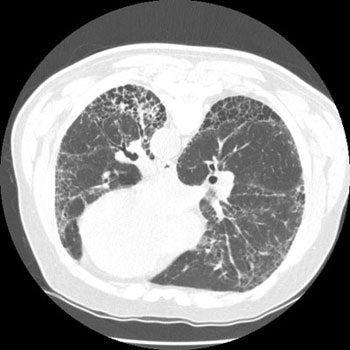

The patient below had severe interstitial lung disease. An ill-defined density was detected in the left lower lobe- a bronchogenic carcinoma was subsequently diagnosed. Patients with interstitial lung disease are at increased risk for developing bronchogenic carcinoma:CXR reveals interstitial lung disease and a soft tissue mass in the left lung:

CT scan demonstrates honeycombing and other characteristic findings of UIP. The mass could be seen arising in an area of severe honeycombing: